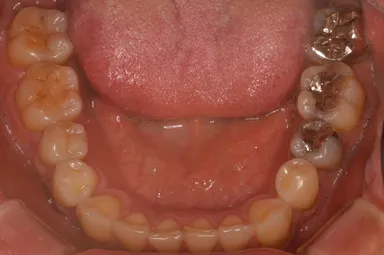

現代人に多い歯並び

「理想的な歯並び」と「現代人に多い歯並び」の画像、これは何を意味しているのか?

歯並びの中にあるもの。それは、「舌」だったのです。

歯並びが小さいと「舌が窮屈」になり、アゴの位置がずれてしまいます。